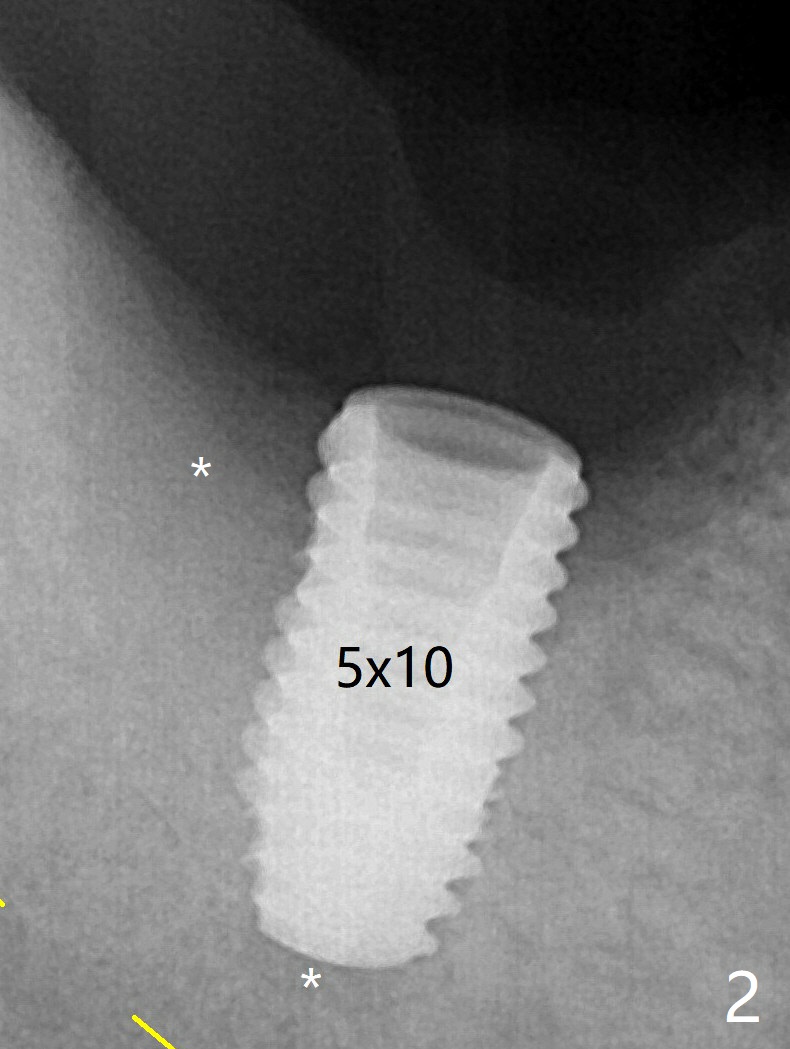

Slow Gentle Osteotomy Last Next  第二磨牙即种 全景片 #18 5个月结果